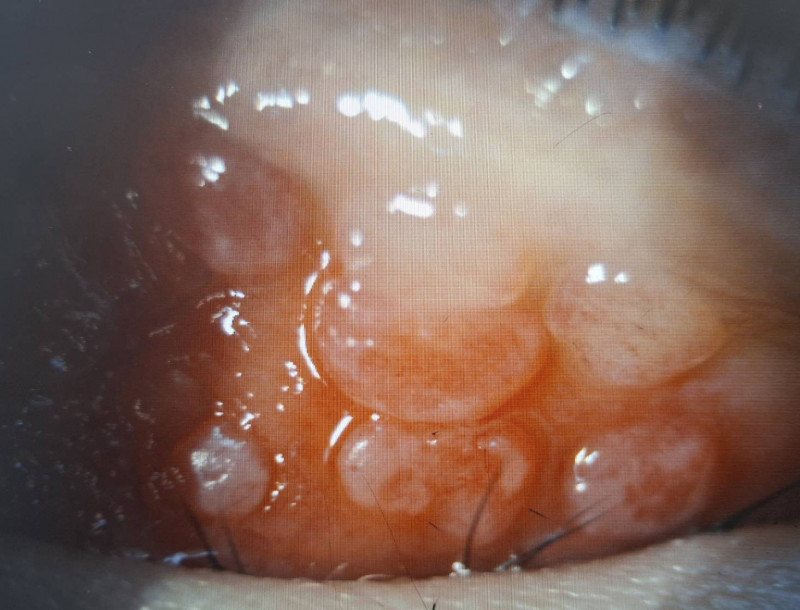

〔記者許麗娟/高雄報導〕1名國小二年級男童近半年來常覺得左眼非常癢而不斷眨眼、揉眼,近日左眼眼瞼嚴重腫脹家長帶他就醫,檢查發現上眼瞼結膜充血外,還長了許多巨大的疙瘩物,每顆直徑都大於0.1 公分,並覆蓋白色黏液,診斷為「巨大乳突結膜炎合併角膜潰瘍」,醫師提醒,孩童若不斷眨眼就應儘快就醫檢查。

達特楊眼科聯盟執行長洪啟庭指出,小二男童就醫時不僅左眼眼瞼嚴重腫脹,最佳視力僅0.5並有300度散光,應是過敏性結膜炎合併過敏性鼻炎、濕疹、異位性皮膚炎或氣喘等,因為長期揉眼導致眼皮長滿巨大乳突,因長時間壓迫造成上半部角膜有淺層潰瘍,故造成300度的高度散光和視力模糊,經強效抗生素與適當類固醇藥水治療,2星期後角膜潰瘍痊癒,乳突的也變小,學童眨眼睛的現象也明顯改善,但乳突完全消失恐要半年以上。

洪啟庭表示,台灣地區每3個學童就有1位罹患短期或長期性過敏性結膜炎,短期多是季節性過敏,長期性因慢性發炎,使結膜上皮細胞的過度增生,如本案男童長成大於0.1公分的乳突,病人會有明顯的異物感、激癢、黏液分泌物變厚、視力模糊,嚴重時還會出現角膜潰瘍。成人大多是和隱形眼鏡配戴習慣不良有密切關係,學童多為過敏反應。